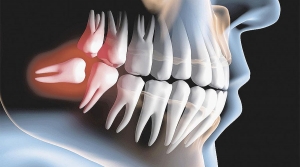

Mostrando itens por marcador: Extrair o Siso